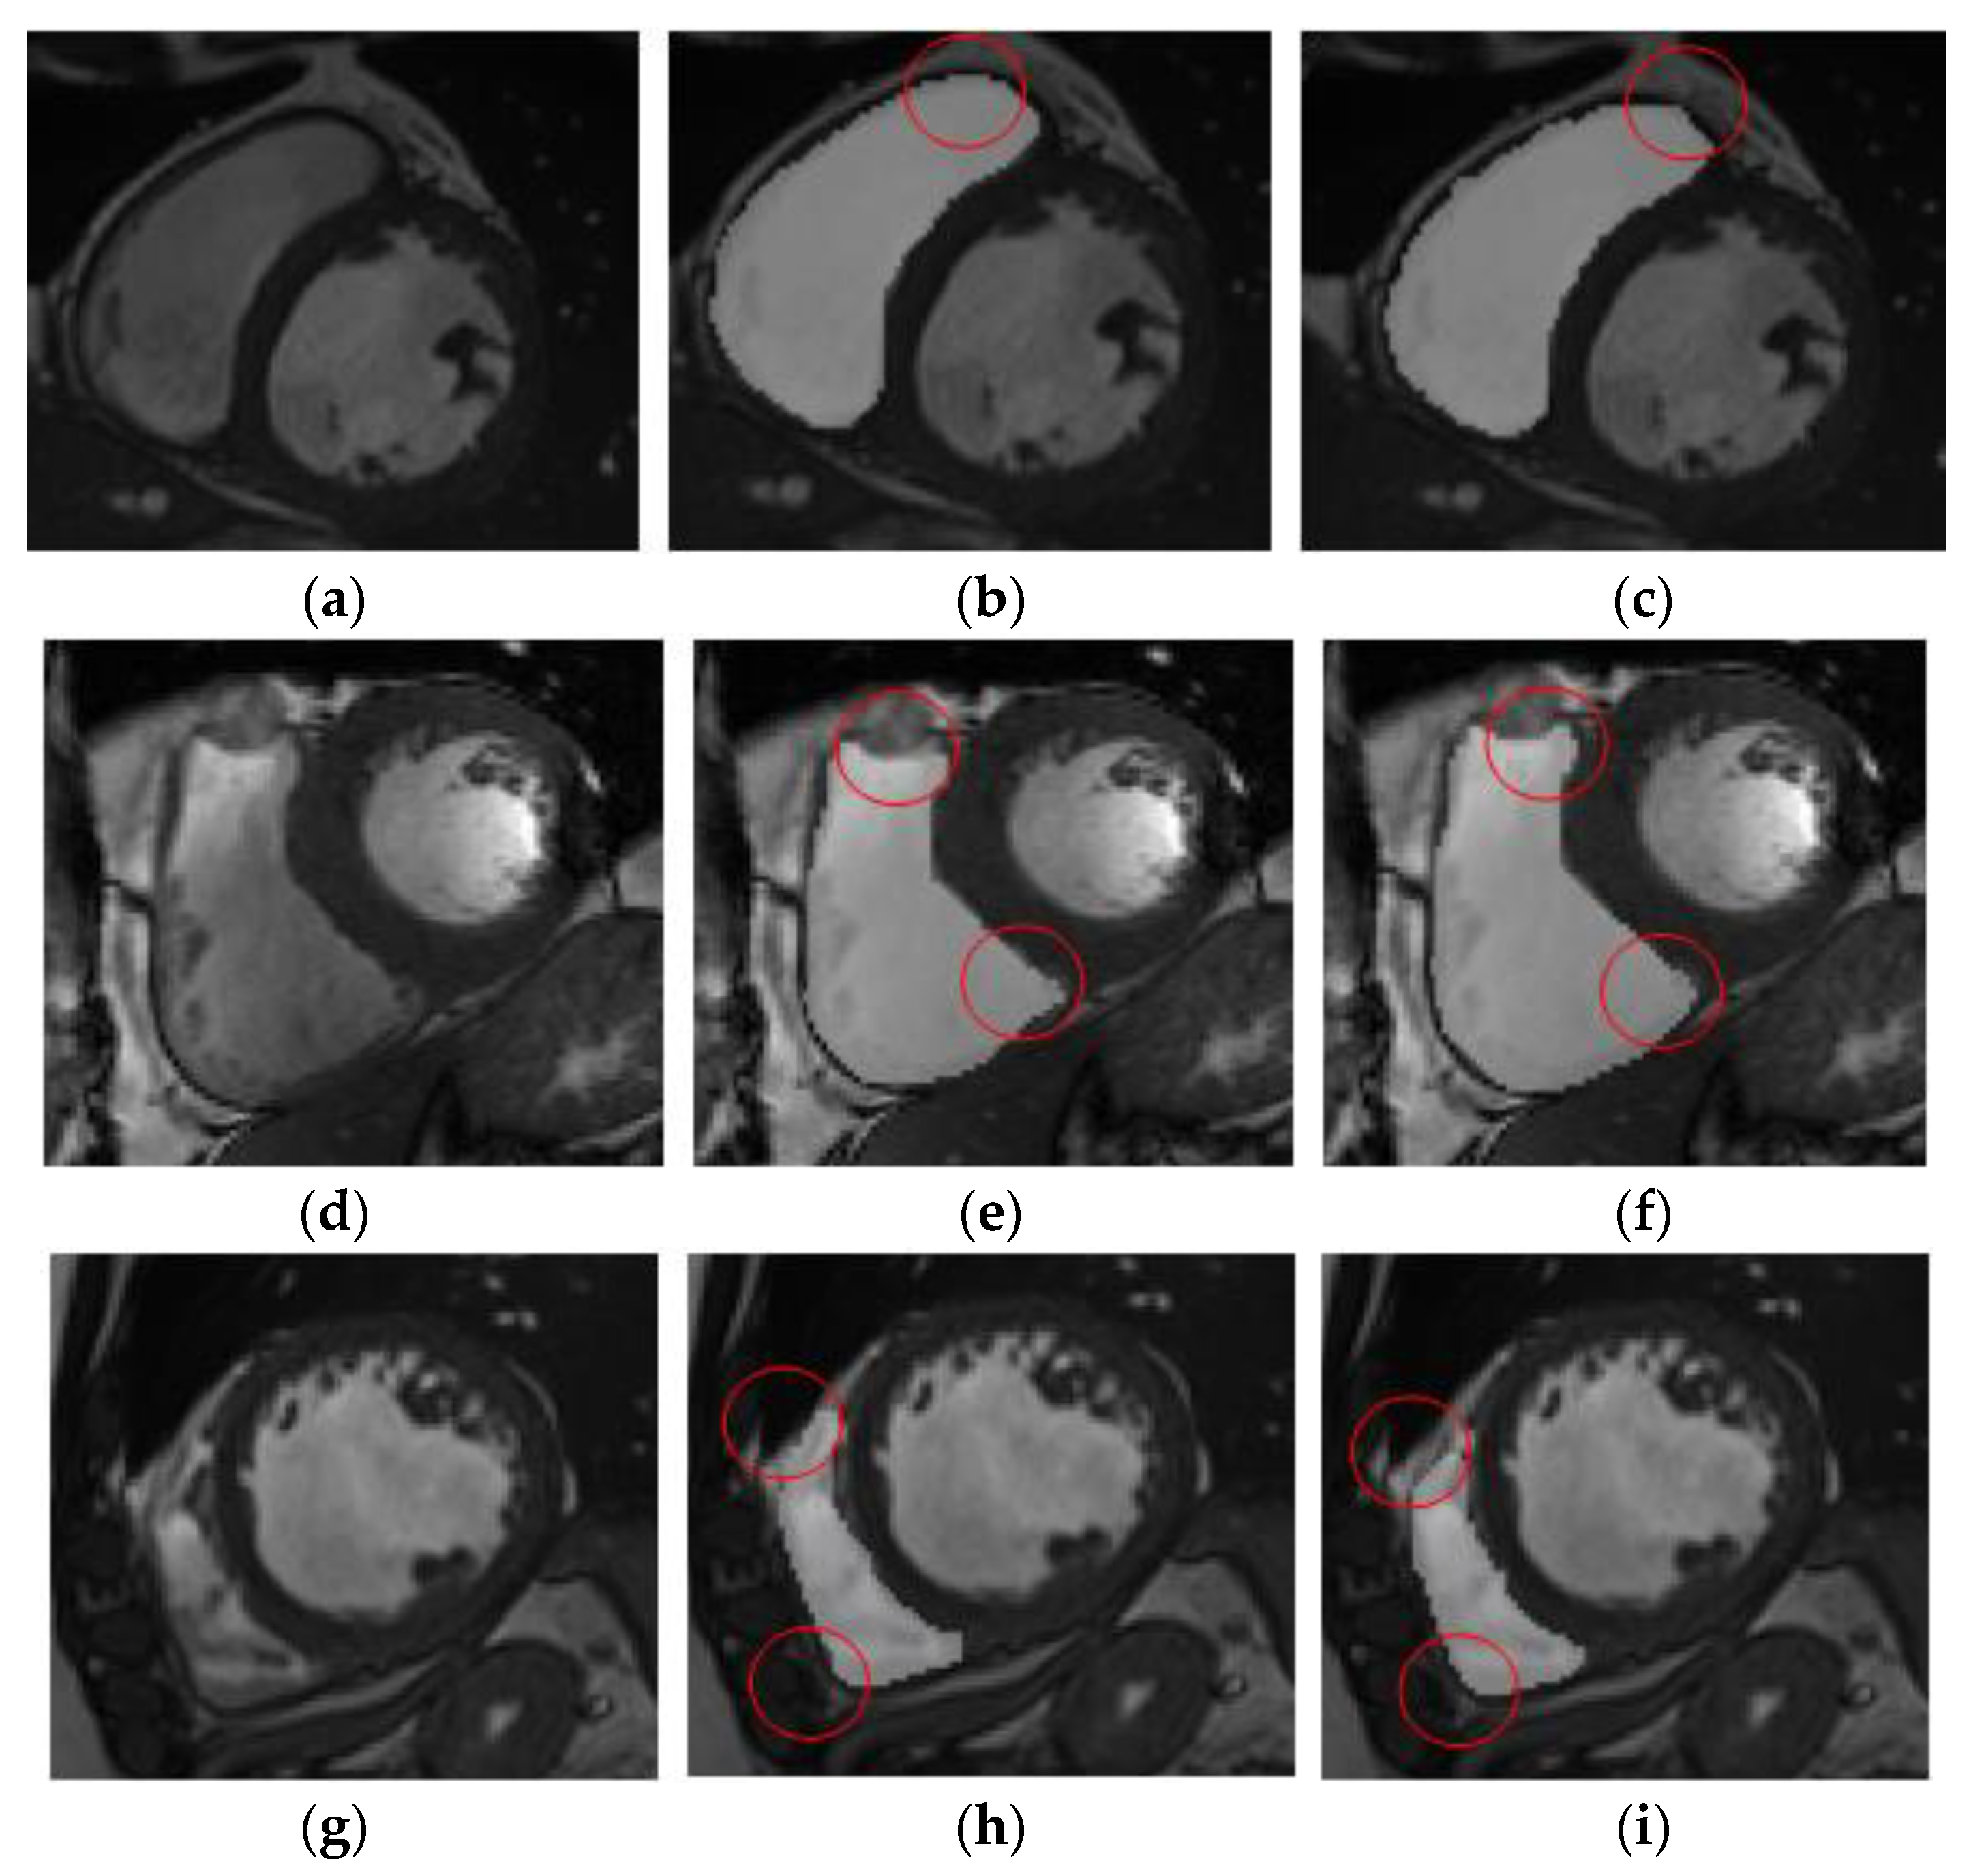

The results of right ventricle segmentation by the RAU-Net network are shown in Figure 8, which shows two groups of images, each of which is divided into three groups. Figure 8a,d are the input feature images, Figure 8b,e are the resulting images of the U-Net network segmentation, and Figure 8c,f are the gold-standard images marked by experts. The position shown in the red circle represents the difference between the gold-standard image and the segmentation prediction area.

Figure 8. Comparison of network segmentation results. (a) Input feature images 1. (b) Resulting images of the U-Net network segmentation 1. (c) Gold-standard images marked by experts. (d) Input feature images 2. (e) Resulting images of the U-Net network segmentation 2. (f) Gold-standard images marked by experts.